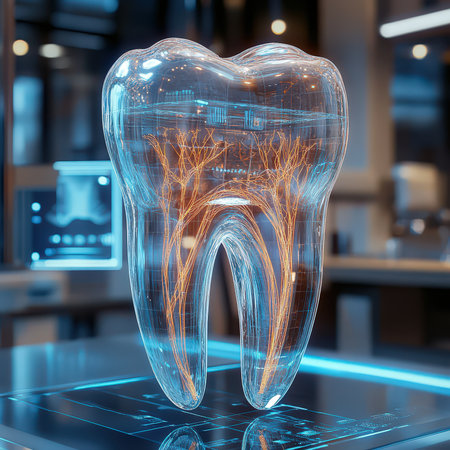

Detailed anatomical model showing human tooth structure, emphasizing root canal system. Ideal for educational purposes in dental hygiene and anatomy studies.

A stunning dental model showcases the elegance of stomatology in a serene setting.

This image presents a detailed anatomical model of a human tooth, highlighting its layers in a contemporary dental environment for educational purposes.

Futuristic glowing tooth made of transparent material with light particles, symbolizing advanced dental technology, in a dark, bokeh-lit background.

This image depicts a detailed anatomical model of a human tooth, showcasing the intricate internal structures, including nerves and blood vessels, essential for educational and healthcare purposes.

Transparent tooth model displaying detailed internal anatomy, including nerves, blood vessels, and pulp structure, isolated on a gray background.

High-Resolution 3D Tooth Model with Nerves, Roots, and Holographic Interface

AI generated 3D rendering of a translucent human tooth revealing an intricate glowing neural and vascular network in orange over a deep blue background conveying futuristic biovisual data processing